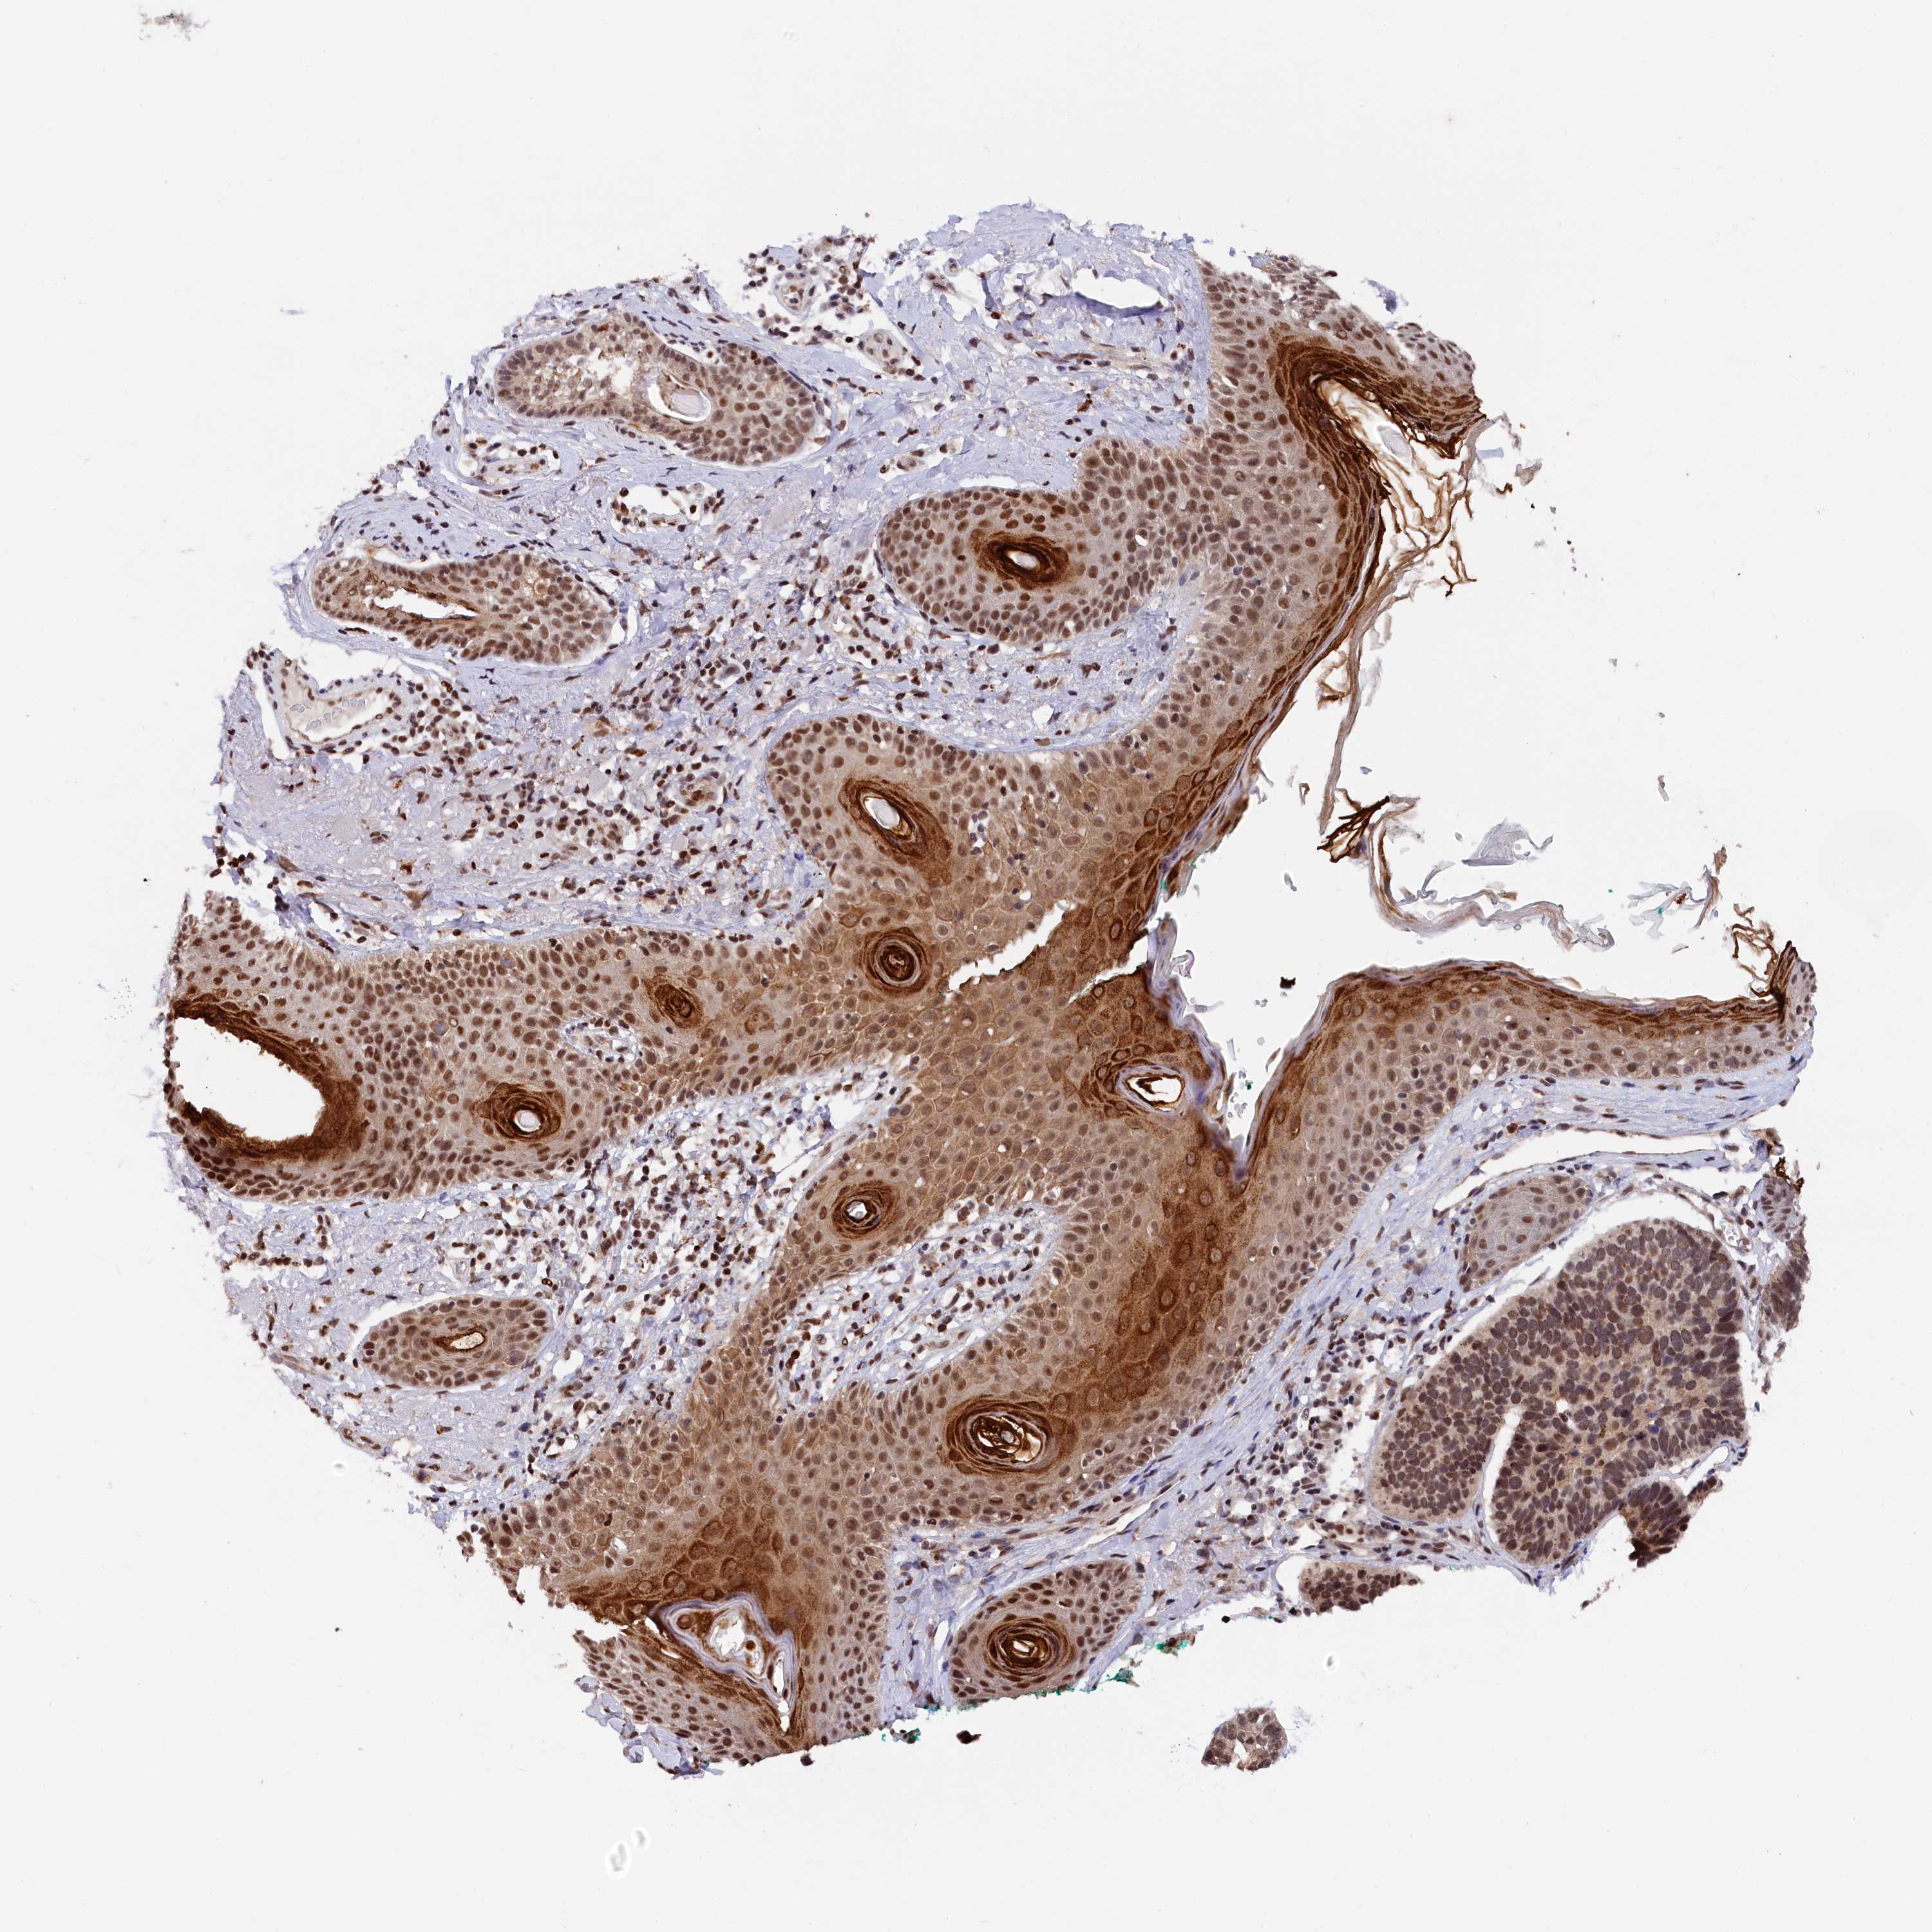

Basal cell and squamous cell cancer

SKIN CANCER - Protein expressioni

A mouse-over function shows sample information and annotation data. Click on an image to view it in a full screen mode. Samples can be filtered based on level of antibody staining by selecting one or several of the following categories: high, medium, low and not detected. The assay and annotation is described here.

Antibody stainingi

Antibody staining in the annotated cell types in the current human tissue is reported as not detected, low, medium, or high, based on conventional immunohistochemistry profiling in selected tissues. This score is based on the combination of the staining intensity and fraction of stained cells.

Each image is clickable and will lead to virtual microscopy that enables deeper exploration of all samples and also displays staining intensity scores, fraction scores and subcellular localization as well as patient and tissue information for each sample.

Antibody HPA041124

Staining

Medium

Moderate

>75%

Nuclear

Squamous cell carcinoma, NOS